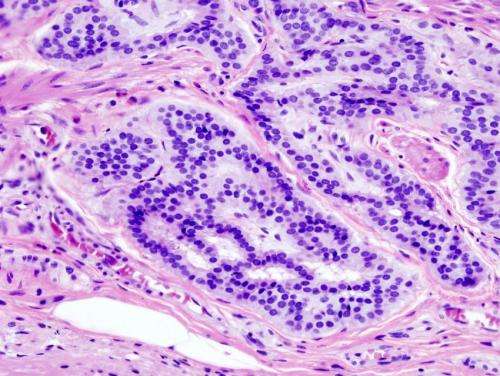

Study identifies risk factors for early onset colorectal cancer in males

Colorectal cancer incidence and deaths are declining for individuals age 50 and older, but are increasing for those under 50.

A new study, led by researcher-clinician Thomas Imperiale, M.D., of the U.S. Department of Veterans Affairs, Regenstrief Institute and Indiana University School of Medicine, identifies seven risk factors for early onset colorectal cancer in males. The risk evaluation model the researchers developed may help 45- to 49-year-olds accept and adhere to new national screening recommendations and may also identify younger men for whom earlier screening should be considered.